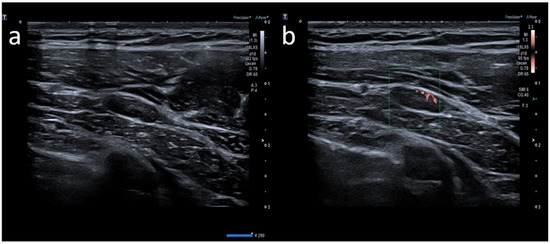

Atypical Sites of Lymphadenopathy after Anti-COVID-19 Vaccine: Ultrasound Features

- Cocco, G.; Pizzi, A.D.; Fabiani, S.; Cocco, N.; Boccatonda, A.; Frisone, A.; Scarano, A.; Schiavone, C. Lymphadenopathy after the Anti-COVID-19 Vaccine: Multiparametric Ultrasound Findings. Biology 2021, 10, 652. [Google Scholar] [CrossRef] [PubMed]